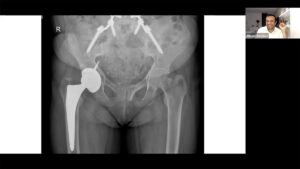

Aqui você encontrará conteúdos atualizados sobre a Quantica, sobre técnicas cirúrgicas, planejamento ortopédico, mobilidade, casos clínicos e inovações em saúde. Ideal para médicos, fisioterapeutas, distribuidores e também para pacientes em busca de informação qualificada sobre reabilitação ortopédica.